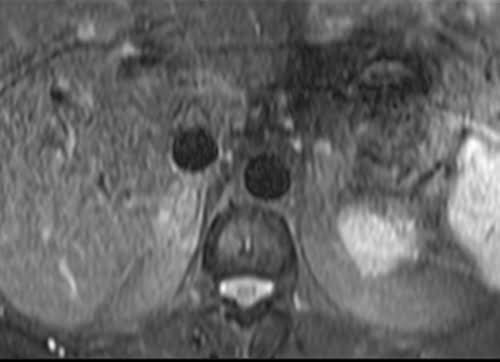

Adrenal MRI T2 TSE fat sat axial images